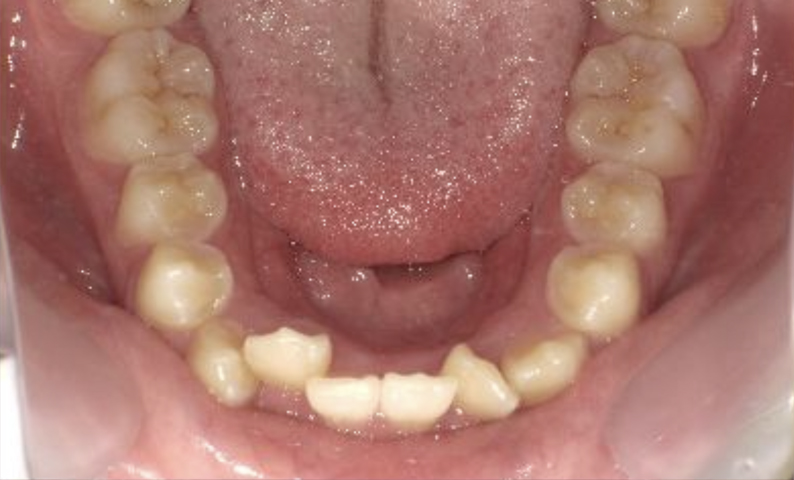

症例_001 下顎だけの部分矯正

治療期間:6ヶ月金額:27万円+税女性前歯のガタガタ下の前歯だけ

| Before | After |

|---|---|

|